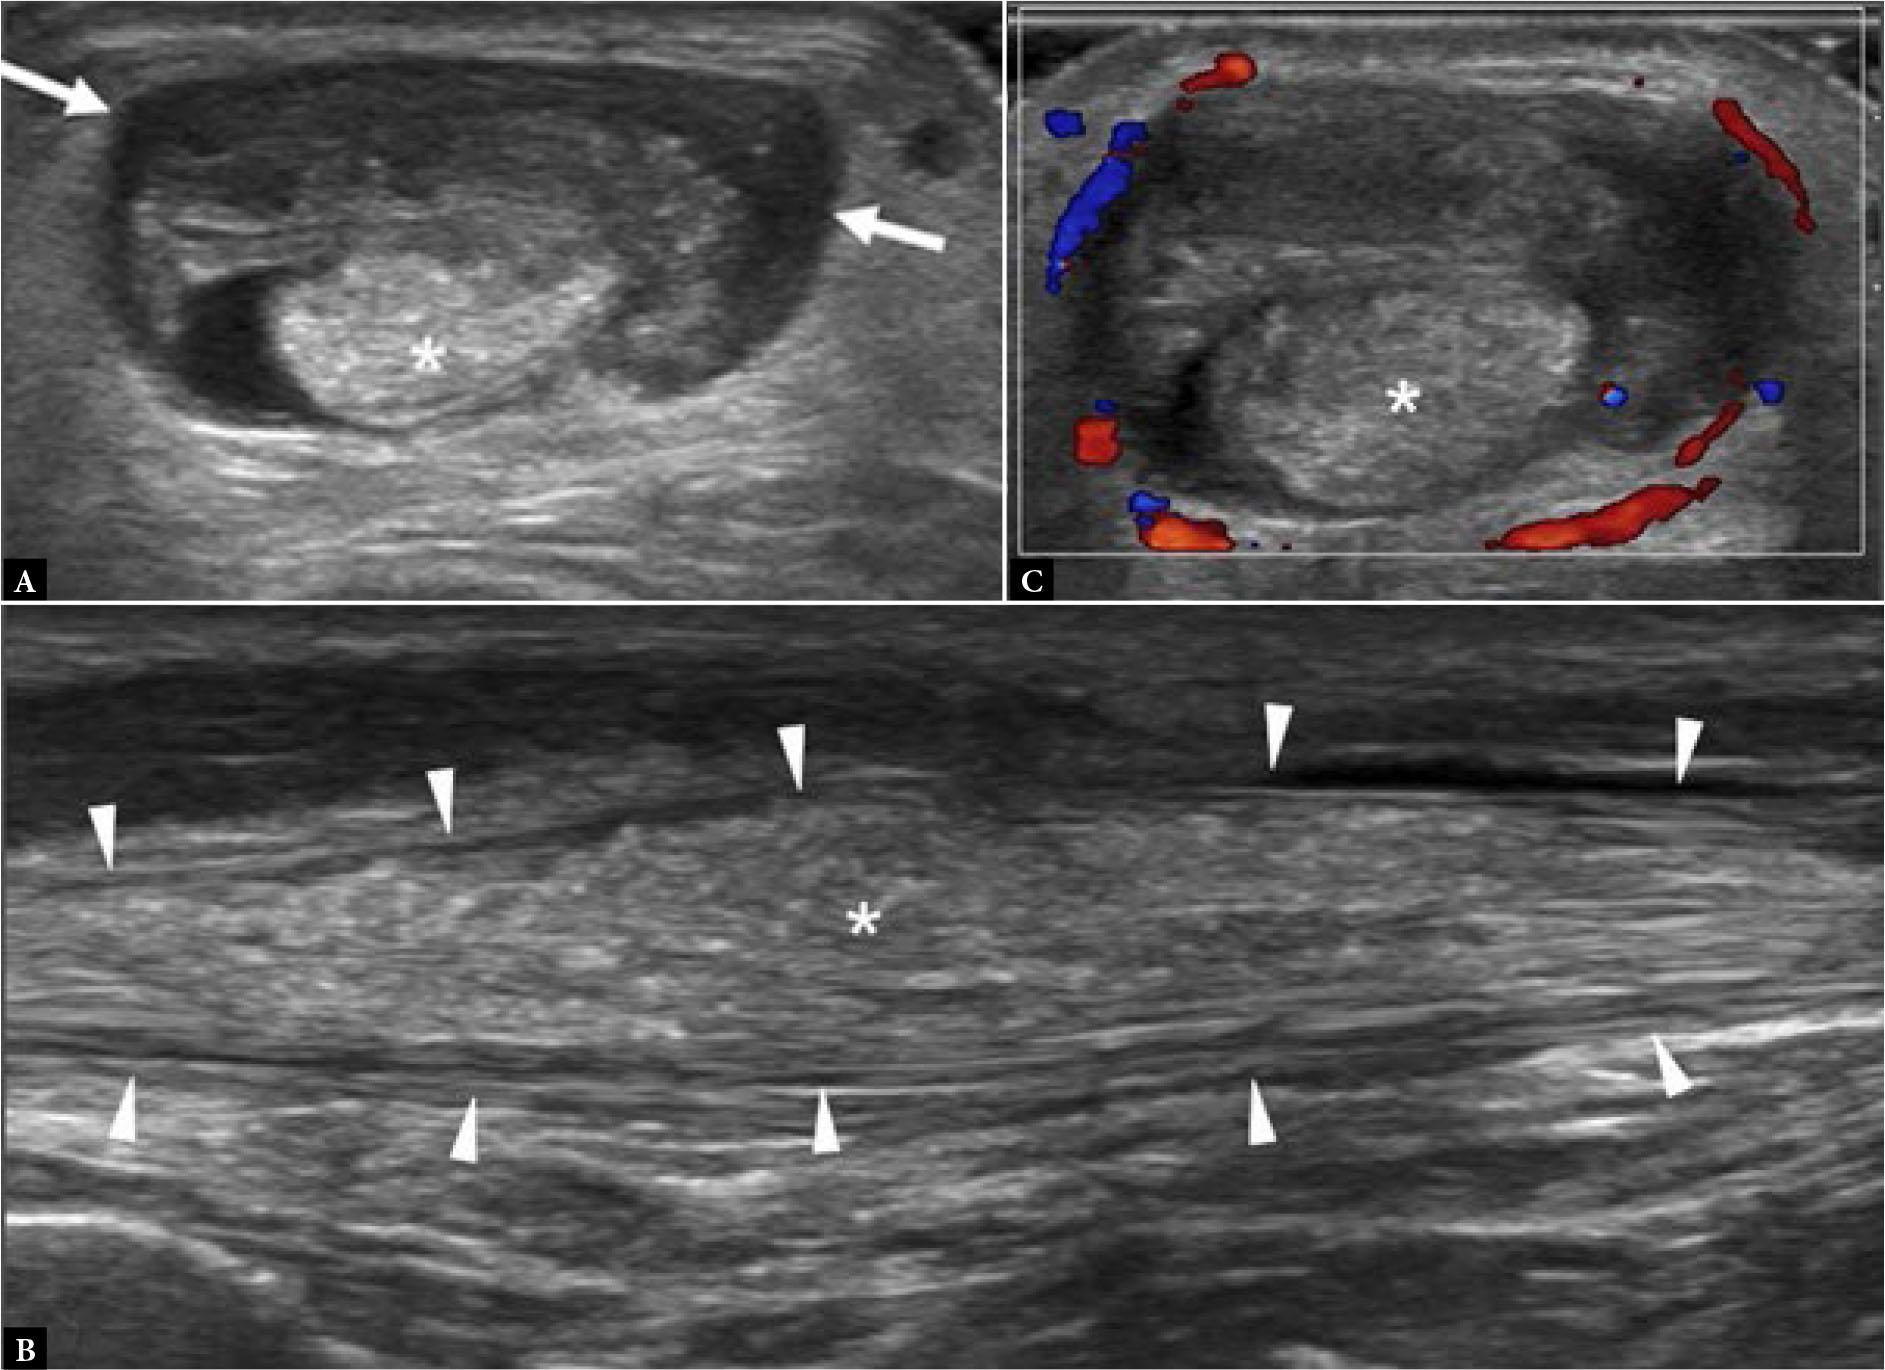

Stress fractures typically occur in young to middle-aged individuals undertaking unaccustomed high levels of exercise over an extended period. The 2nd and, less frequently, the 3rd metatarsal mid-shafts are commonly affected sites(1) (Fig. 1). The base of the 2nd metatarsal is splinted between the distal end of the medial cuneiform and the 3rd metatarsal bone. It is also a key weight-bearing bone, making it more susceptible to injury. The 1st, 2nd and 5th metatarsal bases, the navicular, cuneiform, cuboid, and medial sesamoid bones are additional common sites of stress fractures in the mid- and forefoot(1,2) (Fig. 2). Radiographs are normal in the earliest stages of stress fracture. US at this juncture may reveal a cuff of echogenic thickening due to thickened periosteum (‘periostitis’) around the cortex of the affected bone area. The cortex may be less distinct than usual, together with juxtacortical soft tissue edema and hyperemia (Fig. 1). While such findings are non-specific, they are usually diagnostic in the appropriate clinical setting without the need for additional imaging other than radiographic follow-up. MRI will provide even earlier detection of stress fracture than US, revealing focal bone marrow edema (BME) at the affected site, often with a thin hypointense fracture line(1) (Fig. 2). In the appropriate clinical setting, BME on fat-suppressed, fluid-sensitive sequences without a visible fracture line is termed a ‘stress reaction’ rather than a ‘stress fracture’(1). Radiographs and US will typically be normal in stress reaction. It is important to correlate any BME with clinical symptoms, as BME may occur due to physiological bone remodeling without necessarily being reflective of an injurious stress reaction(3).

Fig. 1.

41-year-old female with forefoot pain and swelling for one month. There was no specific traumatic event and no undue sporting activity. A tendon injury was suspected clinically A. Dorsoplantar (DP) radiograph shows normal 2nd metatarsal bone (arrowhead). B. Longitudinal greyscale and C. color Doppler, and D. transverse greyscale US images show moderate severity localized periosteal thickening (open arrow) of the 2nd metatarsal shaft dorsally, with moderate adjacent soft tissue thickening (open arrowhead) consistent with active stress fracture. E. Radiograph three months later showed marked periosteal thickening of the 2nd metatarsal shaft (arrow) compatible with healed stress fracture

Lisfranc trauma ranges from ligamentous injury to complex fracture-dislocations. It may occur acutely, following high-speed injury, or insidiously, as in diabetic midfoot osteoarthropathy. The Lisfranc ligament complex has three components, with the interosseous component being the strongest and the dorsal component being the weakest (Fig. 7, Fig. 8)(7). The strong intercuneiform ligament between the medial and intermediate cuneiform bones also indirectly helps stabilize the Lisfranc articulation(7). In patients undergoing surgery for suspected Lisfranc injury, the interosseous Lisfranc ligament was torn in 100%, the dorsal component was torn in 75%, and the intercuneiform ligament was torn in 25%(7). Ligament injury can be isolated or associated with severe fracture-dislocation. Conventional foot radiographs are the first-line imaging modality. In patients with high energy trauma, the diagnosis is usually obvious, and CT will help with surgical planning(8). In patients with low-energy injury, bilateral weight-bearing radiographs are helpful at detecting subtle subluxation, though obtaining standing radiographs is often impractical in the acute setting. CT will reveal nondisplaced fractures and subtle subluxation that may be overlooked radiographically (Fig. 9)(8). Weight-bearing CT is also feasible(9). On ultrasound, only the dorsal component of the Lisfranc ligament complex can be reliably seen. Both feet should be compared. Ultrasound signs of a Lisfranc injury include a thickened or absent dorsal ligament, with or without a medial cuneiform-2nd metatarsal distance of >2.5 mm which may further widen on weight-bearing(10). A normal dorsal Lisfranc ligament does not exclude additional ligament injury(8). MRI reliably demonstrates all of the Lisfranc and inter-cuneiform ligaments and is the non-operative gold standard for diagnosing ligament injury (Fig. 8)(8).

Fig. 7.

Schematic diagram of Lisfranc ligament complex shows dorsal (arrow), interosseous (*) and plantar (arrowheads) components of Lisfranc ligament. Cm, medial cuneiform, MT2, second metatarsal base, MT3, 3rd metatarsal base